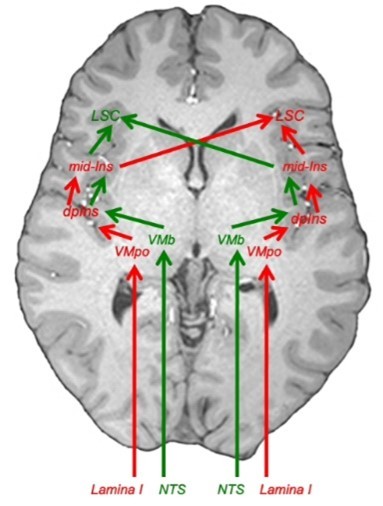

Beskriv övergripande banan för interoception upp till och med interoceptiva kortex och limbiska motorkortex

Thalamokortikala förbindelser

Beskriv dessa olika typer av förbindelser och vad det är viktiga för gällande interoception

Förklara interoceptionens lateralisering, utgå från lamina 1

Sammanfatta vad som sker i mid-insula

Så anteriora insula (limbiska sensoriska kortex) får alltså inflöde av interceptiv (och annan) information från mid-insula liksom inflöde av all möjlig information från andra delar av hjärnan